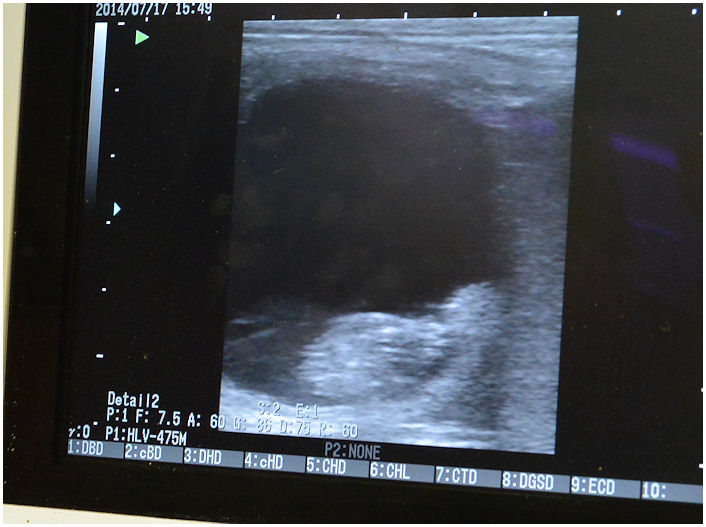

| Op 17 juli is paardje Madelief nog een keer gescand, voor de zekerheid, en het minipaardje is al goed gegroeid! |

| Bij de paardenkliniek in Emmeloord |